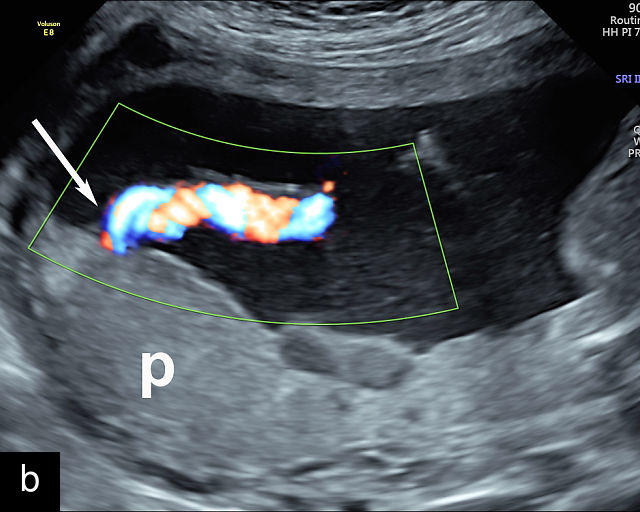

20

(a–c) Grayscale (a) and color Doppler (b,c) ultrasound images of velamentous cord insertion. The cord inserts into the membranes (arrow), from where unprotected fetal vessels (arrowheads) traverse the membranes to insert into the edge of the anterior (a,b) or posterior (c) placenta (p). (d) Color Doppler ultrasound image of velamentous cord insertion, showing the cord inserting into the membranes posteriorly (arrow), from where unprotected fetal vessels (arrowheads) traverse the membranes to insert into the edge of the anterior placenta (p). (e) Ultrasound with color Doppler showing velamentous vessels (arrow) running through the dividing membrane in a dichorionic diamniotic twin pregnancy. The right image shows the placenta after delivery.